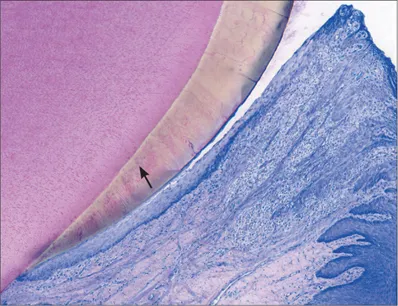

Fig 3 Higher magnification. Supra-alveolar soft tissue comprising the junctional epithelium and root cementum with inserting collagen fibers. Well-encapsulated minor inflammatory cell infiltrate (arrow) located adjacently to the junctional epithelium.

Fig 4 Higher magnification. Oral sulcular epithelium and junctional epithelium. The apical extension of the junctional epithelium ends at the cementoenamel junction. The well-encapsulated inflammatory cell infiltrate (arrow) is clearly distinguishable next to the junctional epithelium.